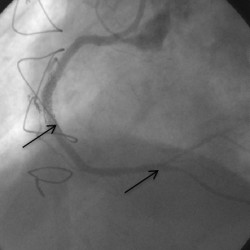

Bypass ameliyatı olmuş bir hastanın sağ damara bacaktan alınarak bağlanan bypass damarı

Daha önce bypass ameliyatı olmuş bir hastanın sağ damara bacaktan alınarak bağlanan bypass damarı tıkanmış. Sağ damar orta yerinden (1. ok) uç kısmına (2.ok) kadar tam tıkalı, uç kısmı sol taraf damardan yan kılcal damarlar ile hafif doluyor.